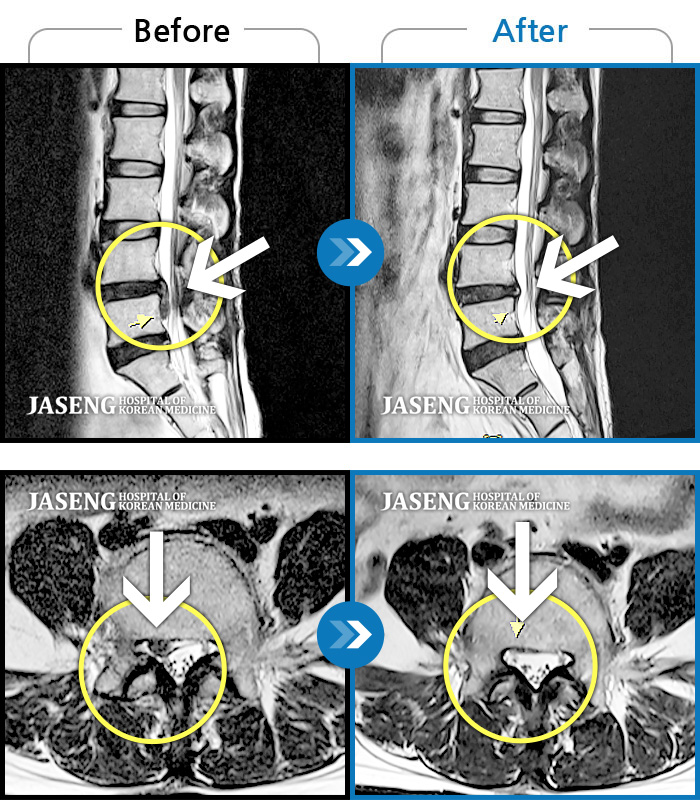

허리디스크

도움받은 사례

광주 · 장영우 원장

양측 허리부터 좌측 다리까지 이어지는 저림과 통증으로 걷기 힘들어 내원하였습니다.

촬영시기

2024.11.22 ~ 2025.05.16

2025.05.30